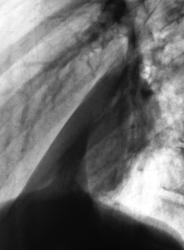

"Красивая" пневмония.

Пациент направлен на исследование врачом терапевтом с диагнозом "пневмония". Клиника пневмонии наличествует.

сегментарная пневмония (8 сегмент) с плевральным выпотом по глвной междолевой щели.

Очень слабая динамика.